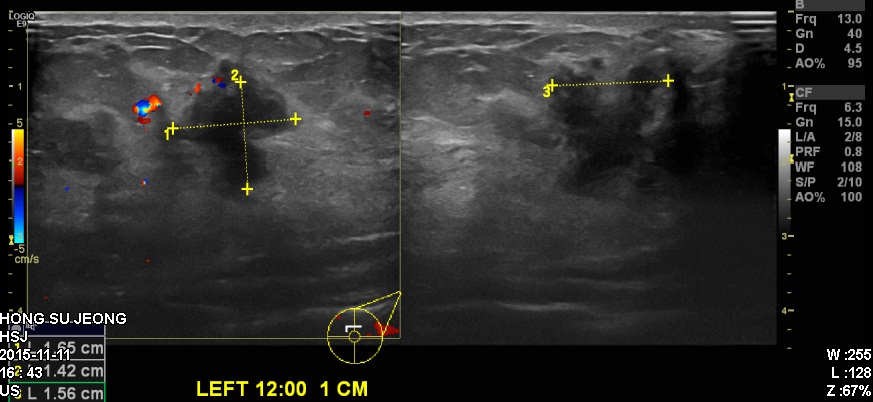

좌측유방에 만져지는 멍우리로 내원하신 40대 환자분이십니다.

본원 유방초음파에서 확인되는 좌측12시 방향의 혹을 조직검사 시행하였고

결과상 침윤성유관암 진단되었습니다.